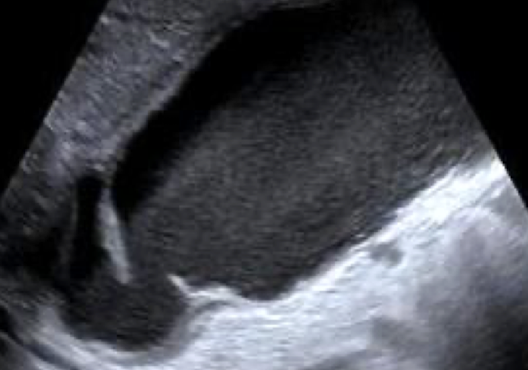

gangrenous cholecystitis

necrotic GB due to prolonged infection

s/s: painful

SONO: thickened irregular edematous wall; pericholecystic abscess; perforations; echogenic densities that fill the lumen of the GB that has:

no shadow

not gravity dependent

no layering effect due to increased viscosity of the bile